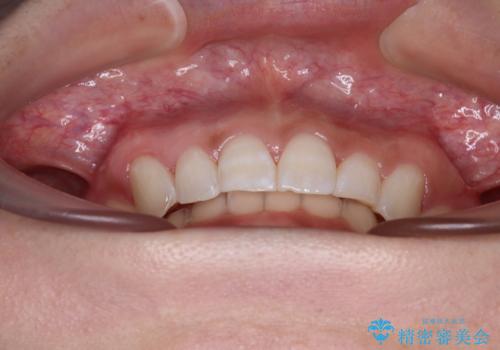

前歯のデコボコを治したい インビザライン矯正治療

上下正中位置は、治療開始時よりは改善したものの、ここが限界であろうというところでのゴールとなりました。

下顎前歯の大半が隠れている状態ですが、左右への歯ぎしりはスムーズに行うことができ、就寝時には後戻り防止も兼ねて、食いしばり対策としてマウスピースの使用を継続するようお願いしております。